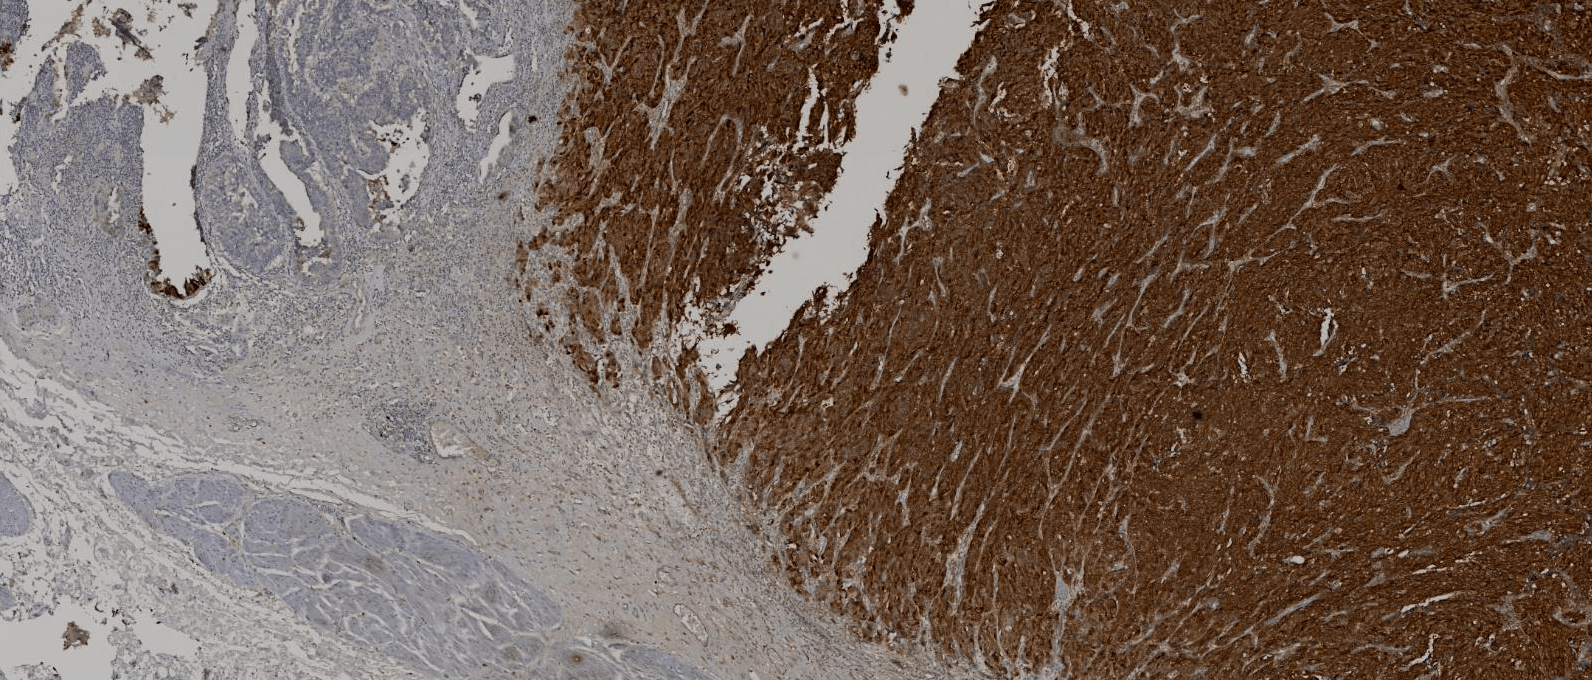

Immunohistochemistry for SV 40 showed diffuse positivity on the tumour cells whereas the non neoplastic urothelium did not stain for SV 40.